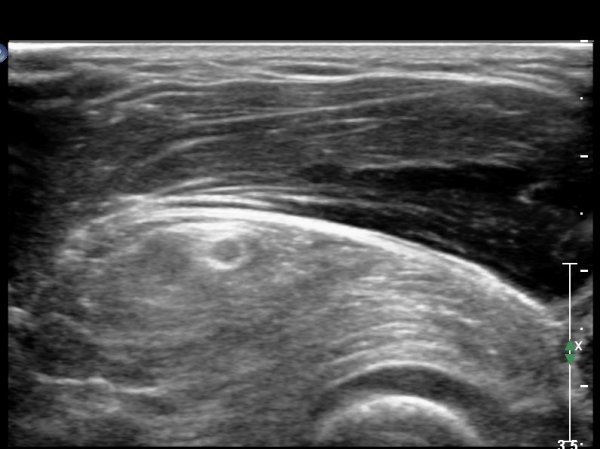

ŽÃËÀÚ¸¦ Á¶±Ý ¸»´ÜÀ¸·Î À̵¿ÇÏ´Ï ¿ä°ñµÎ°¡ °üÂûµÇ°í ÀÌÁú¼º°í¿¡ÄÚÀÇ Á¾±«°¡ Èİñ°£½Å°æÀ» Ç¥ÃþÀ¸·Î ÀüÀ§½ÃŰ´Â

¾ç»óÀ¸·Î °üÂûµÊ(»çÁø 2).